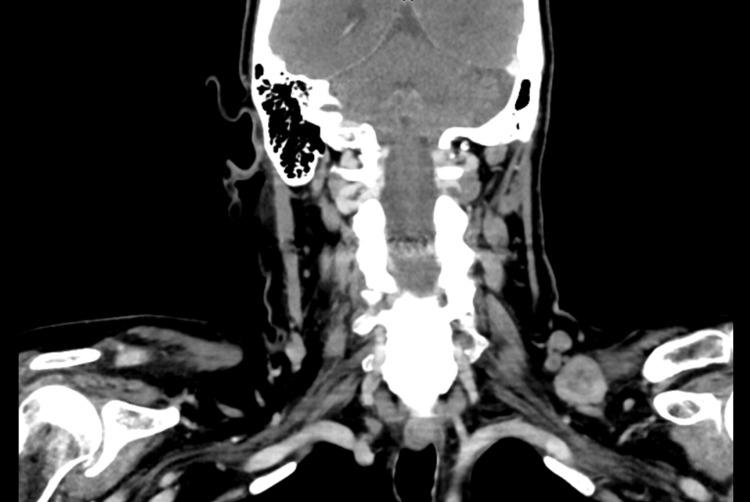

Breast cancer recurrence can occur many years after the initial treatment, particularly in hormone receptor-positive (HR+) cases, where the risk of late recurrence remains significant. Late recurrences are well documented, with research showing that they can happen even decades after the primary diagnosis, necessitating extended monitoring and personalized therapeutic approaches. A 65-year-old woman with a history of stage IIIC invasive ductal carcinoma, initially treated with neoadjuvant chemotherapy, bilateral mastectomies, adjuvant chemoradiation, and prolonged hormonal therapy, presented 10 years later with metastasis to the left supraclavicular lymph nodes. A biopsy confirmed recurrent ER+/PR+/HER2- (estrogen receptor-positive/progesterone receptor-positive/human epidermal growth factor receptor 2-negative) breast cancer. Her treatment was adjusted to include Faslodex (fulvestrant) and Verzenio (abemaciclib), followed by the surgical resection of the metastatic lymph node. Managing HR+ breast cancer involves significant challenges, mainly due to the potential for late recurrence. Even after aggressive treatment and years of remission, dormant tumor cells may become active again, leading to metastasis in less common sites, like the supraclavicular lymph nodes. This situation demands a tailored therapeutic approach, adjusting treatment strategies to address the specific characteristics of the recurrent tumor. In conclusion, late recurrence in HR+ breast cancer requires vigilant long-term follow-up and personalized treatments to effectively manage recurrence risk. Understanding dormancy and reactivation mechanisms is essential for guiding clinical decisions. Prioritizing individualized follow-up strategies and refining treatment protocols will be key to improving patient outcomes and maintaining quality of life.

乳腺癌复发可能在初始治疗多年后发生,尤其是在激素受体阳性(HR+)的病例中,晚期复发风险仍然很高。晚期复发有充分的文献记载,研究表明,它们甚至可能在初次诊断数十年后发生,因此需要延长监测时间并采取个性化治疗方法。一名65岁女性,有IIIC期浸润性导管癌病史,最初接受了新辅助化疗、双侧乳房切除术、辅助放化疗和长期激素治疗,10年后出现左锁骨上淋巴结转移。活检证实为复发性ER+/PR+/HER2-(雌激素受体阳性/孕激素受体阳性/人表皮生长因子受体2阴性)乳腺癌。她的治疗方案调整为包括芙仕得(氟维司群)和唯择(阿贝西利),随后对转移性淋巴结进行手术切除。管理HR+乳腺癌面临重大挑战,主要是因为存在晚期复发的可能性。即使经过积极治疗和多年缓解,休眠的肿瘤细胞可能会再次活跃,导致在不太常见的部位发生转移,如锁骨上淋巴结。这种情况需要量身定制的治疗方法,调整治疗策略以应对复发性肿瘤的特定特征。总之,HR+乳腺癌的晚期复发需要长期密切随访和个性化治疗,以有效管理复发风险。了解休眠和重新激活机制对于指导临床决策至关重要。优先考虑个体化随访策略并完善治疗方案将是改善患者预后和维持生活质量的关键。